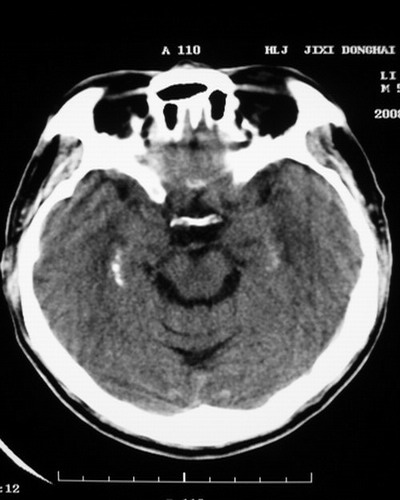

以下是引用随光逐影在2008-1-14 17:26:00的发言:[br]考虑为:甲状旁腺功能低下。需与fahr`s病相鉴别。建议:实验室检查。